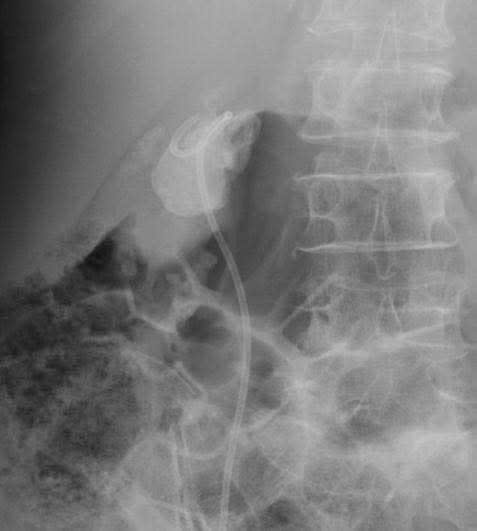

Tại phòng khám Ngoại Tiết Niệu Bệnh viện Đa khoa Xuyên Á, người bệnh được thăm khám và chụp CT, xét nghiệm. Kết quả cận lâm sàng ghi nhận bà T. bị sỏi san hô có đường kính 5cm, sỏi từ bể thận bên phải có nhiều nhánh vào đài thận và hầu hết các đài thận còn lại đều có sỏi, gây nhiễm trùng đường tiết niệu.

Hình ảnh CT cho thấy sỏi san hô bên trong thận